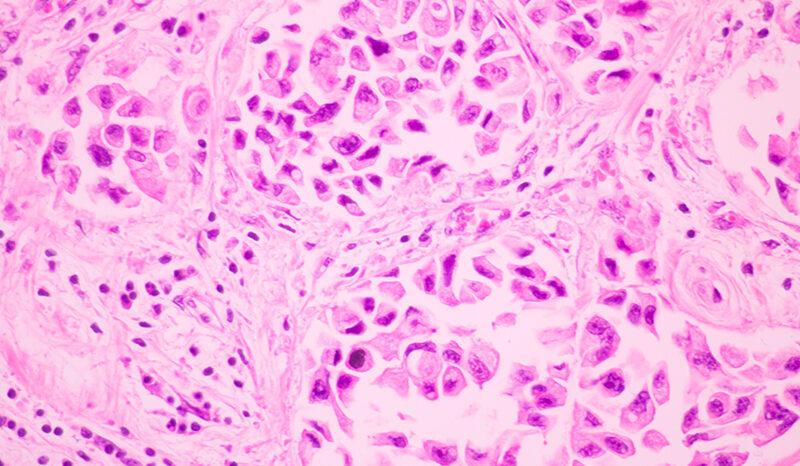

On return to Australia, Professor Jane Visvader and I established a Breast Cancer Laboratory. Our group is studying molecular regulators of normal mammary gland development and cancer, with a particular interest in understanding how mammary stem cells and their progeny contribute to the mammary epithelial cell hierarchy and breast cancer. This work led to the discovery of RANK-positive progenitors as a target for breast cancer prevention in BRCA1 mutation carriers. Our laboratory is also using patient derived xenograft (PDX) and tumor organoid models to test promising anti-cancer agents.

Preclinical studies using BH3 mimetics have led to early phase studies of the BCL2 inhibitor venetoclax in breast cancer.